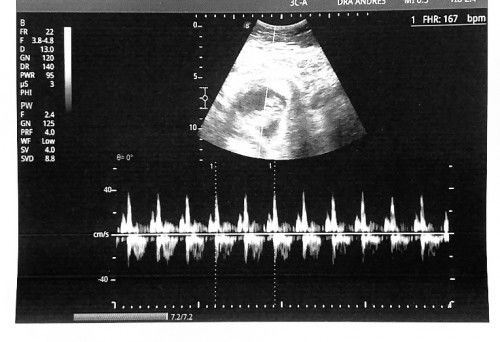

Grabe ang sarap pala sa feeling na marinig yung heartbeat ni baby! Ano pa kaya kapag nandyan na siya sobrang nakaka excite hehe. 11 weeks and 4 days na ako at first time ko marinig yung heartbeat ni baby. Nung nagpa transv kasi ako nung 6 weeks and 7 weeks palang ako hindi pa daw rinig dahil maliit pa si baby. Excited na tuloy ako palagi kada magpapa checkup 🥰 #firstbaby #firsttimemom